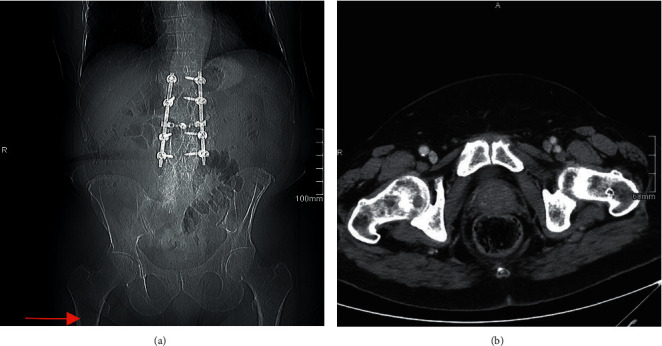

本研究的目的是评估复查童子军CT图像的好处,获得常规肿瘤监测,早期识别病理性骨病变。回顾性分析了2009-2019年在某三级医疗机构接受两名骨科肿瘤外科医生手术治疗的病理性病变或肱骨或股骨骨折患者。我们回顾了影像学记录,以确定该队列中在正式诊断骨病变或骨折之前有CT扫描视图的患者。CT扫描图像由两名独立审查员评估,以确定任何病理病变,并审查x线片报告,以确定在初始扫描解释时放射学是否注意到病变。144例患者被确定,其中39例在正式诊断病变之前有可用的侦察CT图像。25例(64.1%)患者在侦察CT上发现病变,而只有9例(23.1%)患者的病变在最初的CT放射学报告中被记录。研究作者在侦察CT上共发现了29个病变,其中19个(65.5%)在最初的放射学解释中未报告,作者观察到的平均间隔时间为202天正式诊断。在即将发生的骨折中,3名患者(16.7%)在转诊到骨科之前发生了完全骨折,这些在侦察CT上未发现的病变与表现为骨折的平均间隔时间为68天。本研究提倡仔细审查所有的童子军CT成像作为转移性疾病工作的重要组成部分,并鼓励所有从业人员利用这种筛查工具来识别病理性骨病变,这可能有助于加快早期治疗以减少患者的发病率。

The purpose of this study is to evaluate the benefit of reviewing scout CT images, obtained for routine oncologic surveillance, for the early identification of pathologic bony lesions. A retrospective review was conducted on patients who previously underwent surgical treatment by two orthopedic oncology surgeons at a tertiary care institution from 2009-2019 for pathologic lesions or fractures of the humerus or femur. Radiographic records were reviewed to identify patients in this cohort who had available scout views from CT imaging prior to official diagnosis of the bony lesion or fracture. CT scout images were assessed by two independent reviewers to identify any pathologic lesions, and radiographic reports were reviewed to identify if the lesions were noted by radiology at the time of the initial scan interpretation. One hundred and forty-four patients were identified, and thirty-nine had an available scout CT image prior to official diagnosis of the lesion. Twenty-five patients (64.1%) had lesions identified by authors on scout CT versus only 9 (23.1%) who had lesions that were documented in the initial CT radiologic report. There was a total of 29 lesions identified by the study authors on scout CT, and 19 (65.5%) were not reported in the initial radiographic interpretation with an average interval between observation by authors and official diagnosis of 202 days. Of the impending fractures, three patients (16.7%) went on to complete fracture prior to referral to orthopedics with an average interval between these missed lesions on scout CT and their presentation with fracture of 68 days. This study advocates for the careful review of all scout CT imaging as an essential part of the work up for metastatic disease and encourages all practitioners to utilize this screening tool for the identification of pathologic bony lesions which may help expedite early treatment to reduce patient morbidity.